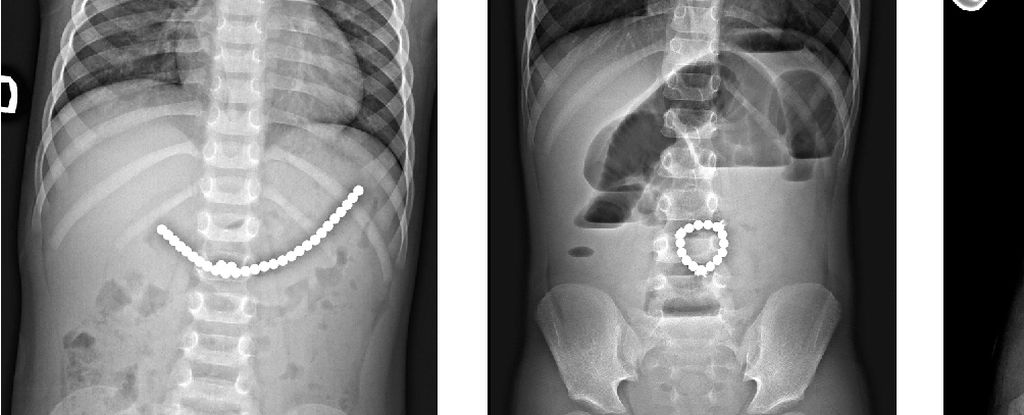

A 13-year-old boy in New Zealand required surgery after ingesting 80-100 small magnets bought from Temu, which caused serious intestinal damage. The case highlights the dangers of high-powered magnets for children and raises concerns about online marketplaces selling hazardous toys, despite regulations and safety standards. Temu stated it is reviewing the matter and cannot verify if the magnets were purchased from their platform.